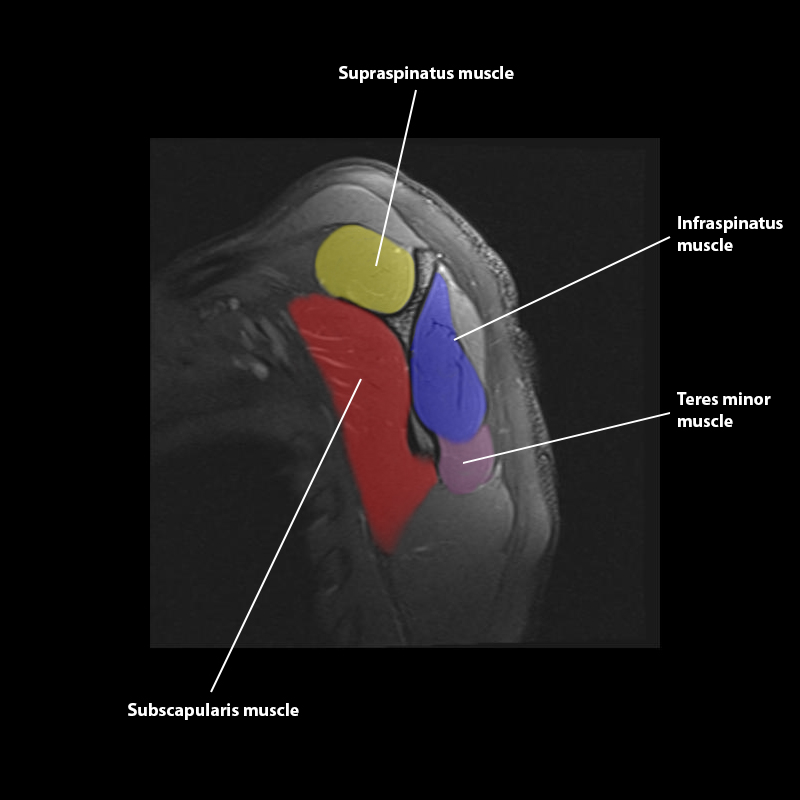

Shoulder MRI Anatomy